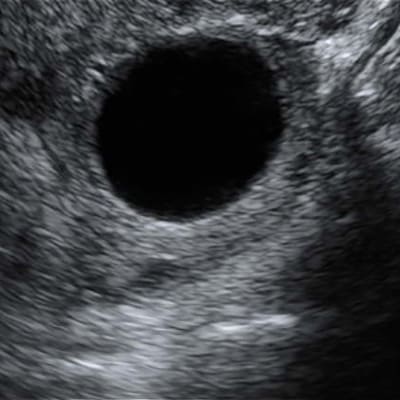

Quistes de Ovario